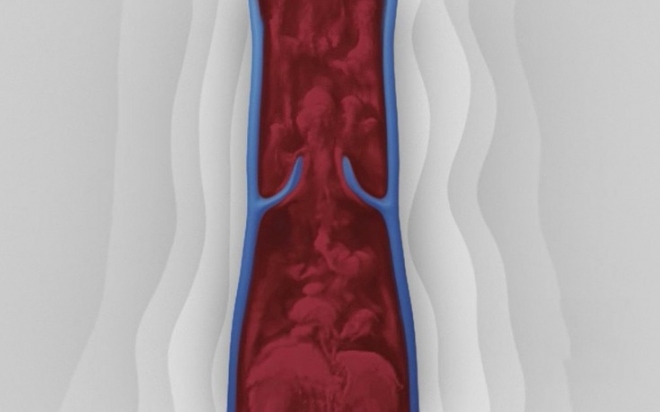

Η εμφάνιση κιρσών είναι συνήθως αποτέλεσμα της φλεβικής ανεπάρκειας του επιφανειακού φλεβικού δικτύου που συναντάται στο 40% των γυναικών και στο 20% των ανδρών. Η ανεπάρκεια των φλεβικών βαλβίδων επιτρέπει την παλίνδρομη ροή αίματος και δημιουργεί συσσώρευση αίματος που λιμνάζει στις φλέβες οι οποίες διαστέλλονται, επιμηκύνονται και αποκτούν σχοινοειδή μορφή με πιθανές ελικώσεις. Οι παθολογικές αυτές φλέβες ονομάζονται κιρσοί.

Εκτός από τους κιρσούς η φλεβική ανεπάρκεια ενδέχεται να προξενεί έντονο πόνο, κάψιμο, αίσθημα βάρους στα πόδια, οίδημα, κνησμό, κράμπες κυρίως κατά τη διάρκεια της νύχτας, αποχρωματισμό του δέρματος, φλεβικά έλκη (ανοικτές πληγές) και θρομβοφλεβίτιδα. Τυχούσα θρόμβωση που θα επεκταθεί από κλάδους (διατιτρώσες φλέβες) προς το εν τω βάθει φλεβικό δίκτυο, εκτός από τη φθορά των φλεβικών βαλβίδων (μεταθρομβωτική ανεπάρκεια) μπορεί να έχει και βαριές επιπλοκές (π.χ. πνευμονική εμβολή).

Παραδοσιακά, η αντιμετώπιση των κιρσών πραγματοποιούνταν με σαφηνεκτομή, μια αιματηρή μέθοδο που απαιτεί νάρκωση και νοσηλεία, έχει μακρά περίοδο αποθεραπείας, και συχνές επιπλοκές (ουλές, τραυματισμό νεύρων, αιματώματα). Βασικότερο όμως πρόβλημα είναι η επανεμφάνιση των κιρσών λόγω του φαινομένου της νεοαγγειογέννεσης.

Η νέα γενιά ανώδυνων laser με ειδικούς ενδοφλεβικούς καθετήρες διπλών δακτυλίων εκπομπής (laser double-ring 360ο) επιτυγχάνει την θεραπεία των κιρσών με τη εφαρμογή ελάχιστης, αλλά απόλυτα εστιασμένης, ενέργειας στα τοιχώματα του αγγείου. Η εστιασμένη δράση του laser συρρικνώνει ομοιόμορφα τα τοιχώματα και σφραγίζει οριστικά και με απόλυτη ασφάλεια την πάσχουσα φλέβα ελαχιστοποιώντας το ενδεχόμενο επιπλοκών (αιματωμάτων, μετεγχειρητικού πόνου, κ.α.).